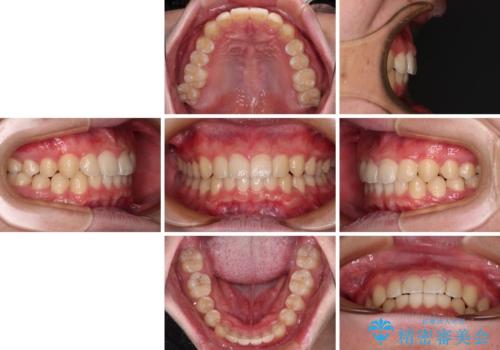

- 前方に傾斜した前歯を気にして来院された患者様です。

強く食いしばってしまう癖があり、下顎前歯に押し出されて上顎前歯が前方へ斜めに突き出している状態でした。

IPR(歯と歯の間を削る)を多用して、インビザラインにて矯正治療を行うこととしました。

口元を引っ込めるためのゴムかけを頑張っていただき、満足のいく上顎前歯の傾斜へ改善することができました。